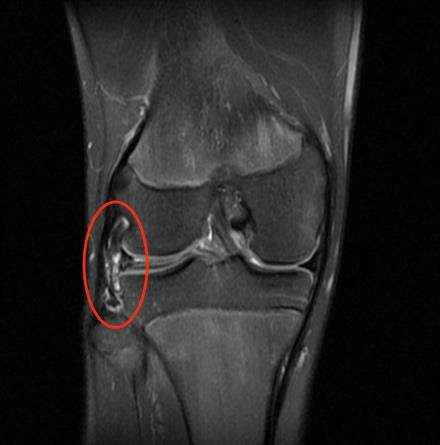

14岁的男孩是个爱运动的初中生,去年10月一次打篮球时,他不小心扭到了右膝,本以为休息几天就好,没想到疼痛一直没消。检查后才发现,问题出在膝盖里一块“不太一样”的软骨——他的外侧半月板天生不是常见的C形,而是更厚、更圆的“盘状”。

盘状半月板(Discoid Meniscus)是一种先天性解剖变异,指的是半月板的形状异常——

正常半月板呈新月形(C形),

而盘状半月板则更厚、更宽,形似半圆甚至满月。

这种异常结构不仅影响膝关节的生物力学,还更容易发生撕裂或引发疼痛,尤其在青少年运动损伤中需高度警惕。

小知识:盘状半月板多见于外侧(外侧盘状半月板),内侧极为罕见。

临床上常用 Watanabe 分型 对外侧盘状半月板进行分类:

手术时间:2024年12月11日

术式:关节镜下部分半月板切除 + 成形术(Saucerization,即“修整为C形”)

手术目标:保留半月板功能,恢复其负荷分散与缓冲作用。